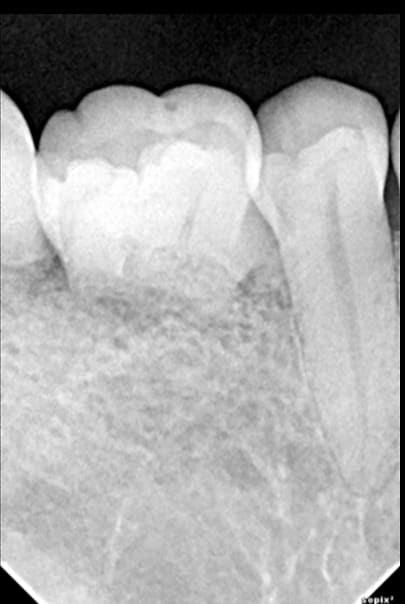

J'ai déjà rencontré ce cas sur un patient homme bien sous tous rapports et que je connais personnellement ( pas de pathologie, ni de problème occlusal, ni de traitement ortho...etc etc....)

Ce sont des résorptions radiculaires externes ou rhizalyses externes non évolutives... Càd que je n'ai pas constaté de diminution des racines au cours des années de suivi...

Ses dents ont super bien tenu même sans racine... détection des résorptions vers 18 ans ( par un autre dentiste que moi ) et elles ont commencées à lui faire bien mal à la mastication vers 46 ans...

A oui impressionnant, ton cas semble bien être des résorptions, moi c'est plutôt une un problème d'édification car on a bien des apex arrondis. De toute façon, c'est sûr qu'il n'y a pas grand chose à faire...